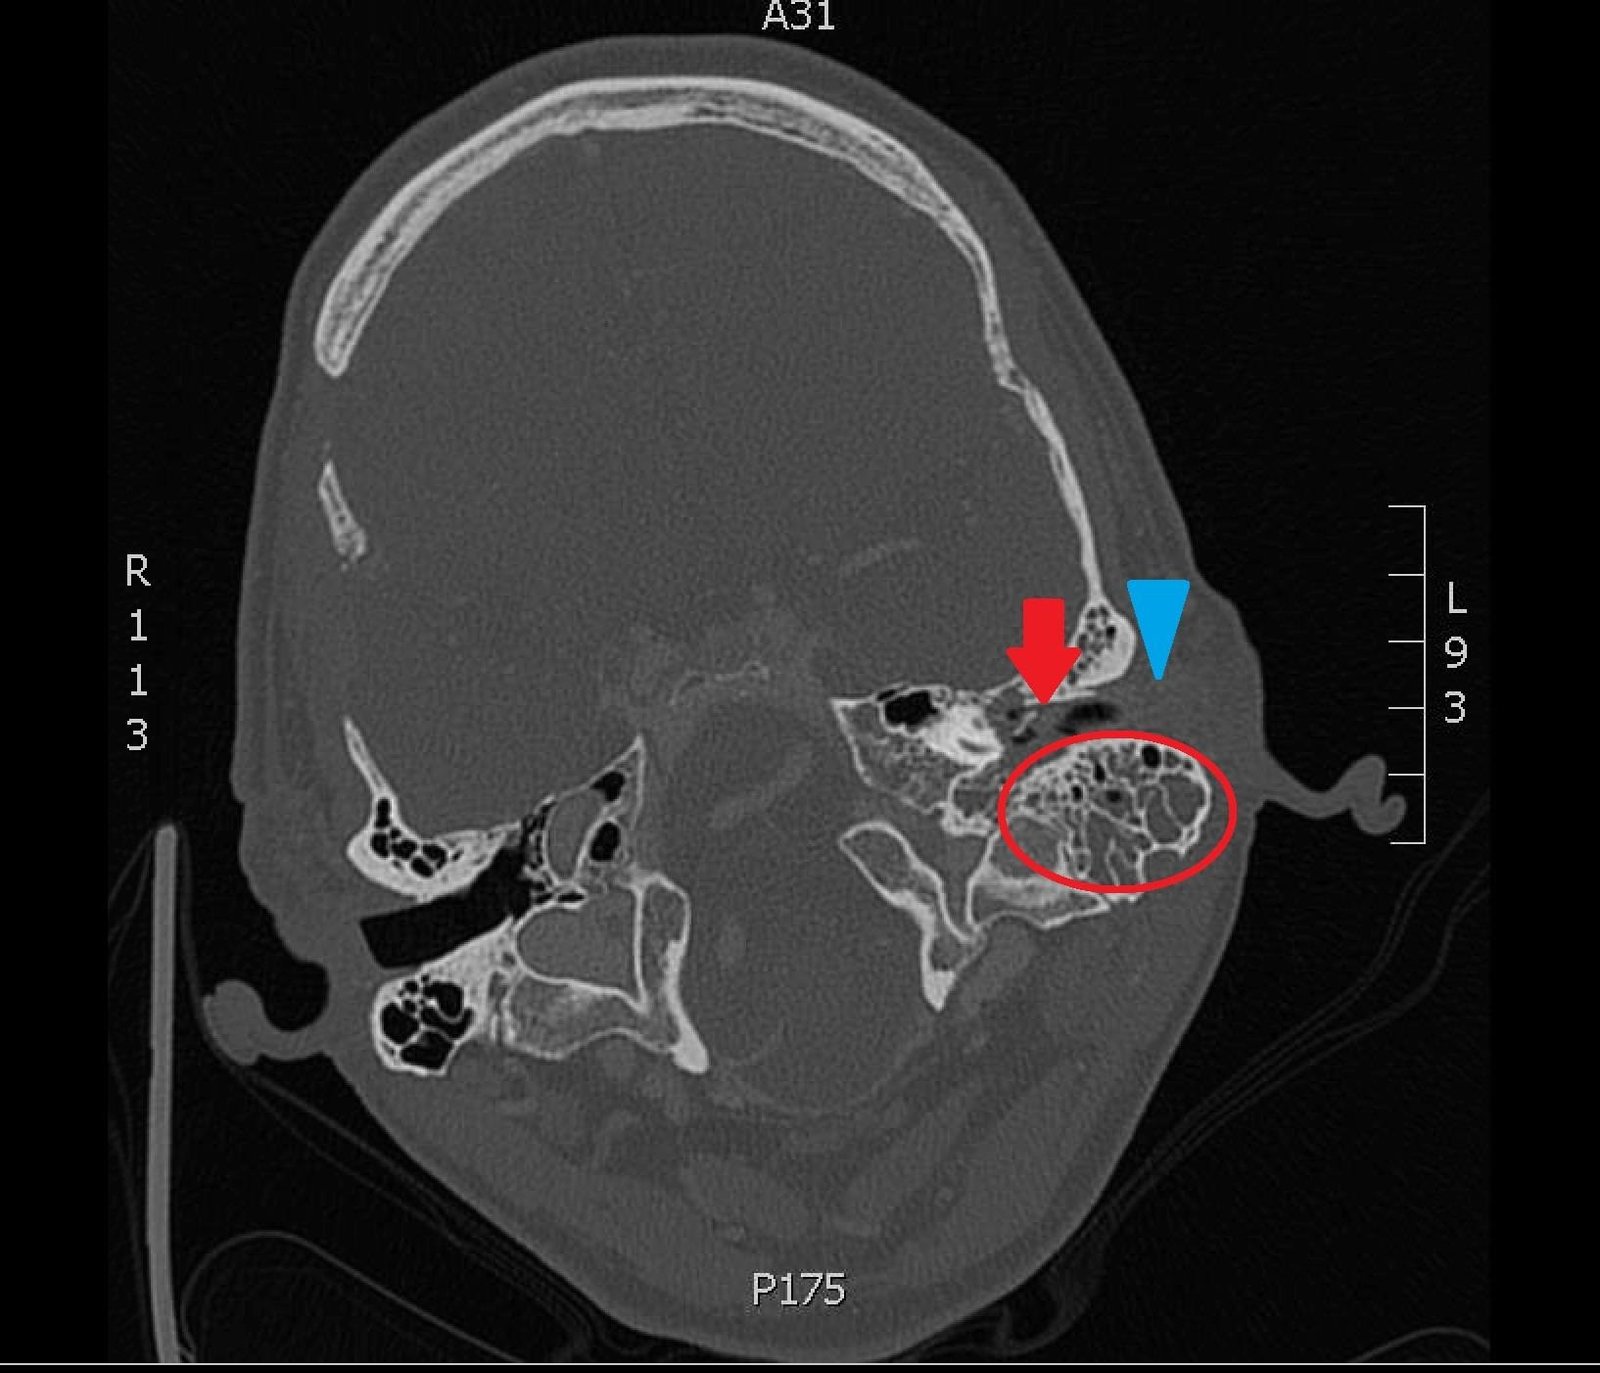

The patient underwent computed tomography (CT) of the head which revealed opacification of the left middle ear (red arrow) and mastoid air cells (red circles). Additionally, there was thickening of the soft tissues of the external auditory canal (blue arrowhead), likely reflecting concurrent otitis externa.  Based on the imaging, he was admitted for findings consistent with acute otomastoiditis.